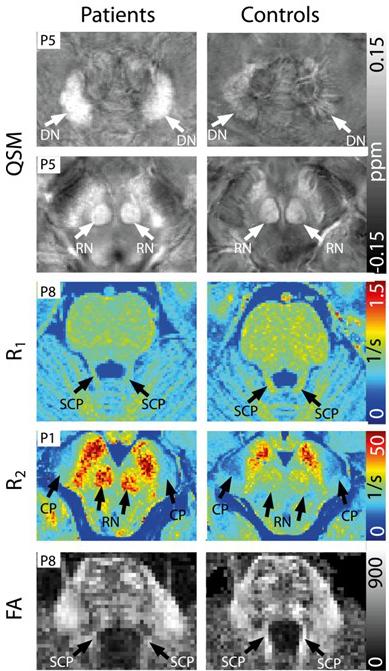

Towards Quantitative Neuroimaging Biomarkers for Friedreich’s ataxia at 7 Tesla

Prof. Gizewski and Dr. Mangesius in cooperation with the German Cancer Research Centre, Heidelberg (Dr. Straub and Prof. Ladd) and PD Dr. Bösch (Neurology Innsbruck)

Modern imaging processes and new imaging techniques with ultra-high field 7T MRI are being investigated. FRDA leads to degenerative cerebral processes. So far, no effective treatment has been found. It is therefore important to aid the development of medication with imaging biomarkers that reflect disease status and progress. MRI data for QSM, R1, R2* and DWI have been acquired at 7T and have facilitated the identification of statistically significant differences between FRDA patients and controls in five out of twelve brain structures (Fig. 4) investigated, which also correlated positively with disease characteristics. Future studies will include the application of these markers in routinely applied 3T field strengths and the investigation of asymptomatic mutation carriers.

- Straub S; Mangesius S; Emmerich J; Indelicato E; Nachbauer W; Degenhardt KS; Ladd ME; Boesch S; Gizewski ER: Towards quantitative neuroimaging biomarkers for Friedreich’s ataxia at 7 Tesla: susceptibility mapping, diffusion imaging, R2 and R1 relaxometry. J Neurosci Res, 2020 Jul 30; 98(11): 2219-31.